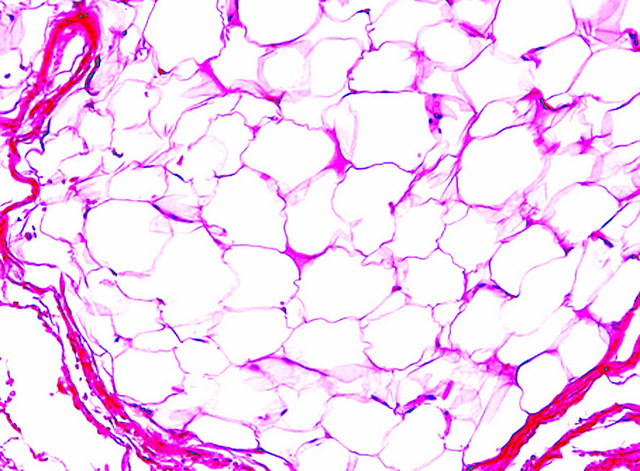

Points of Recognition

- 1Lobules of mature adipocytes

- 2Peripheral (compressed) nuclei

- 3Thin fibrous capsule

- 4Absence of atypia or lipoblasts

- 5Capillaries often present between adipocytes

Lipoma is the most common benign soft-tissue tumour in adults, composed of mature adipocytes arranged in lobules separated by delicate fibrovascular septa. It is characterised by clear cytoplasm and peripherally displaced nuclei with no atypia, mitoses, or lipoblasts.

- Lobules of mature adipocytes with clear (lipid-filled) cytoplasm

- Peripherally located, small, flattened nuclei โ no atypia or hyperchromasia

- Delicate fibrovascular septa separating lobules

- No lipoblasts (distinguish from well-differentiated liposarcoma)

- No increased mitotic activity

- May have thick fibrous capsule or blend imperceptibly into surrounding fat